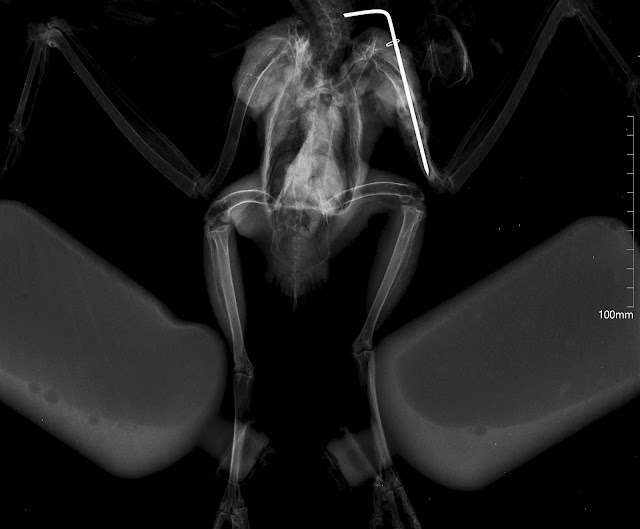

Esta águia-d’asa-redonda (Buteo buteo) ingressou no RIAS com sinais de traumatismo, possivelmente por embate com algum tipo de estrutura.

A fratura que apresentava no úmero direito precisou de correção cirúrgica, e por isso, foi realizado o procedimento e colocadas cavilhas. Para evitar possíveis complicações no pós-operatório, foi-lhe administrado anti-inflamatório e antibiótico durante alguns dias.

| Raio-x realizado durante a cirurgia. |

Algumas semanas mais tarde, as cavilhas foram retiradas e a ave pôde começar a realizar fisioterapia.